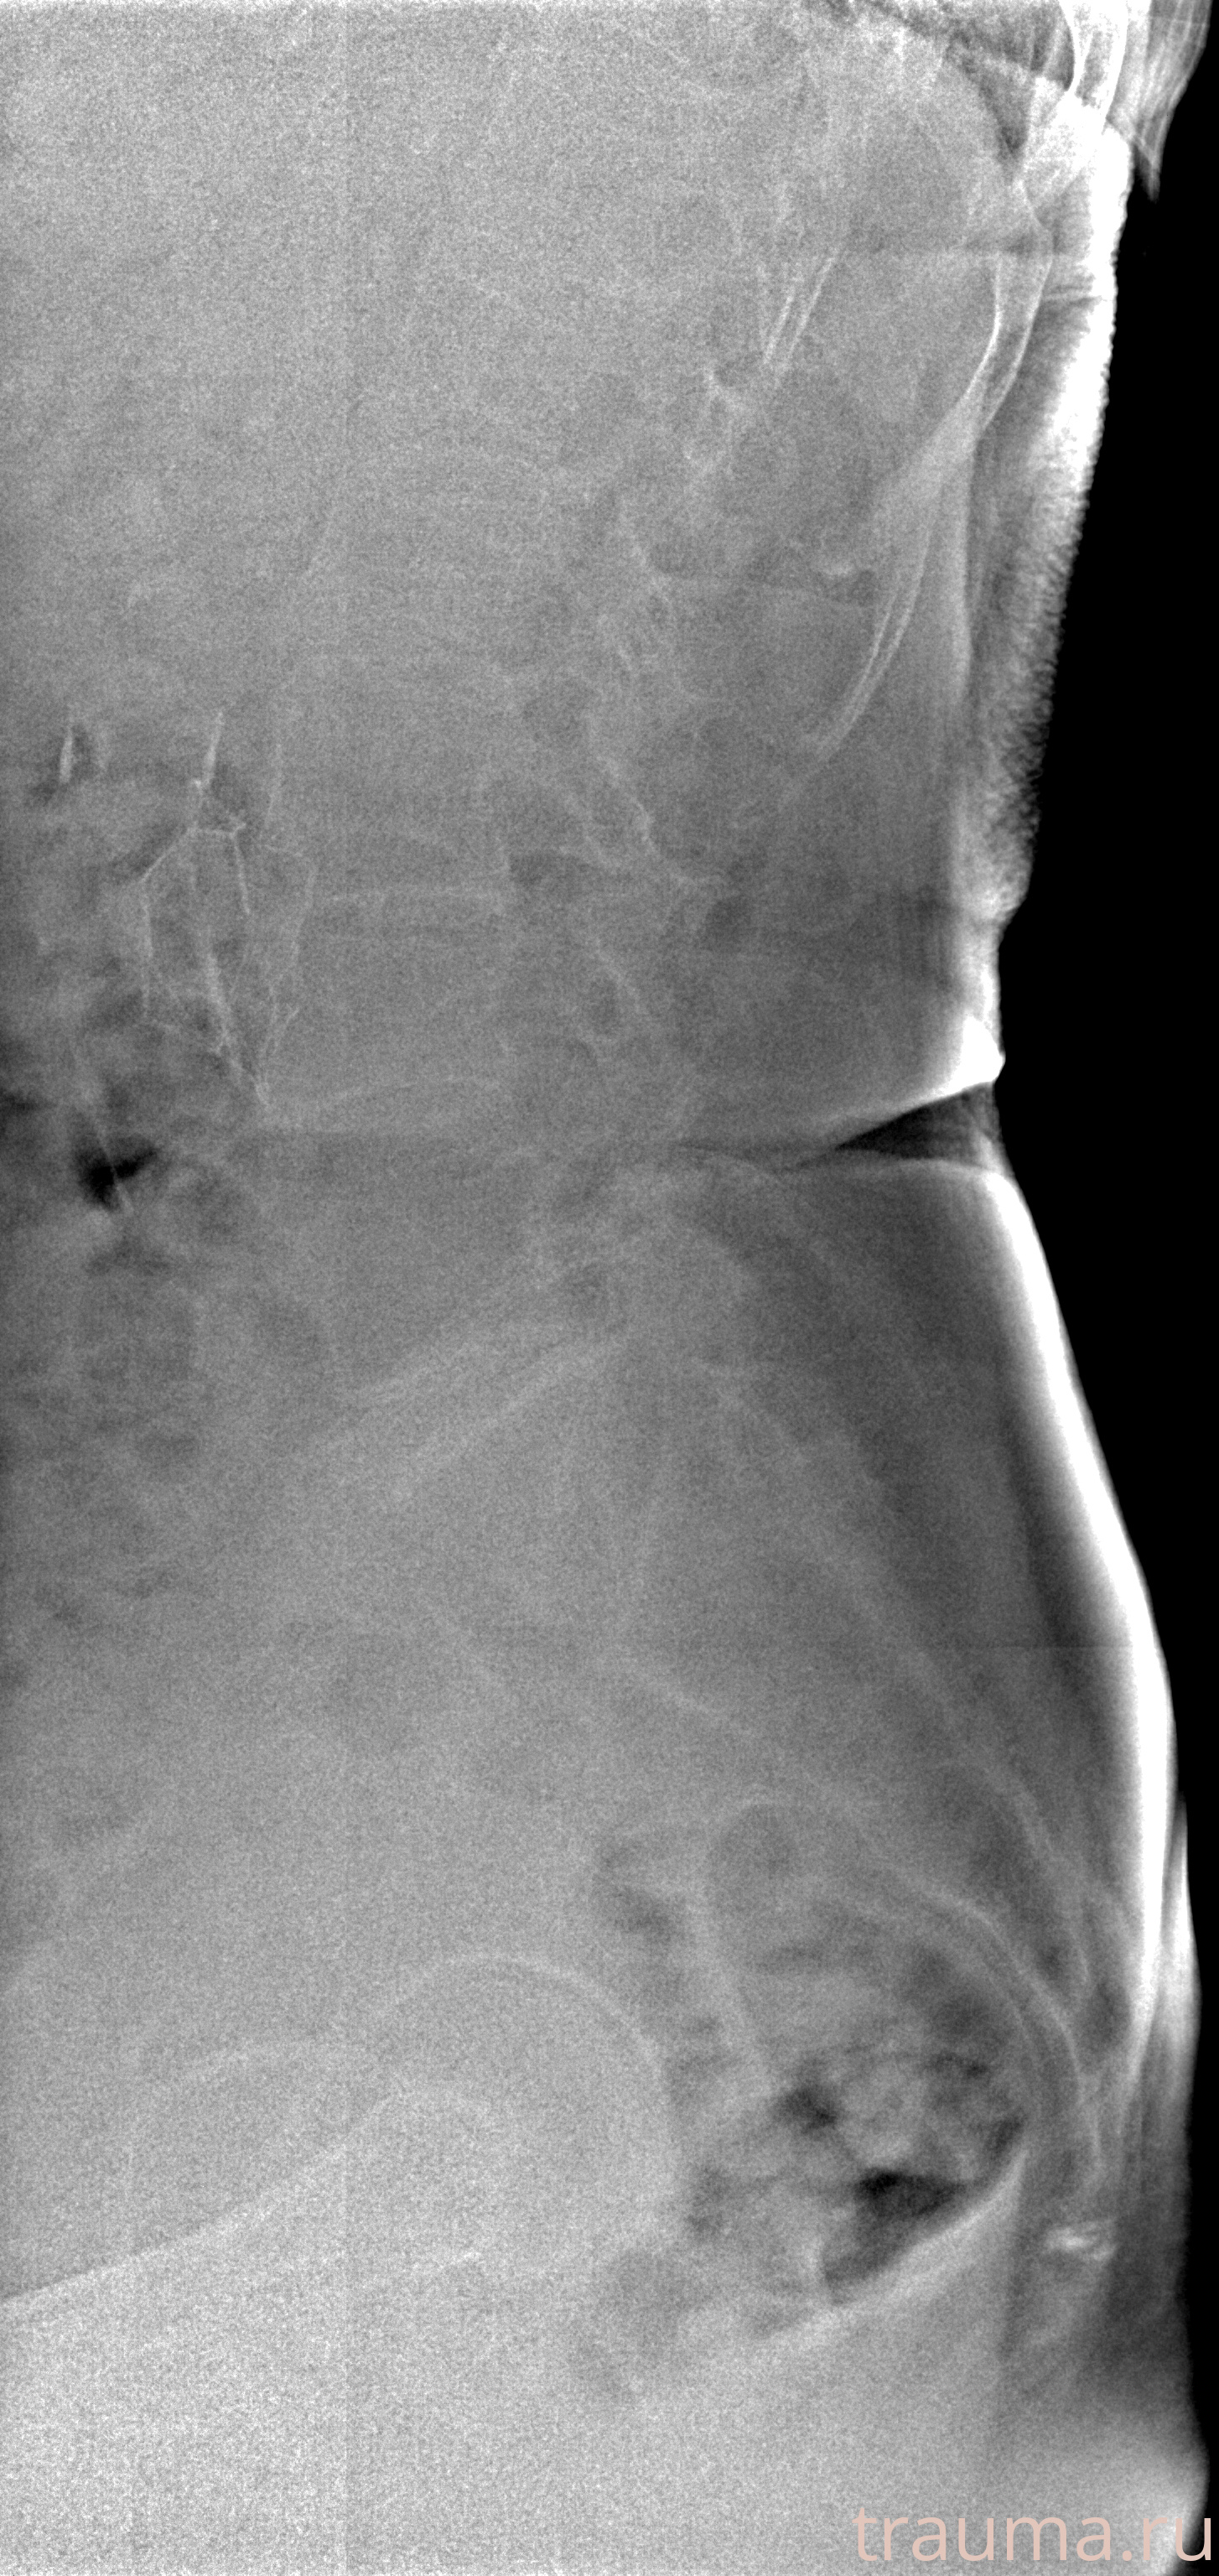

Рентгенограммы

Рентген на дому: по вашему адресу приезжает врач-рентгенолог, травматолог-ортопед с мобильным рентгеновским аппаратом, проводит диагностику травмы или заболевания, делает необходимые рентгенограммы, дает рекомендации по дальнейшему лечению. Получить качественные снимки в домашних условиях возможно благодаря уникальной методике, разработанной МосРентген Центром для института  Склифосовского